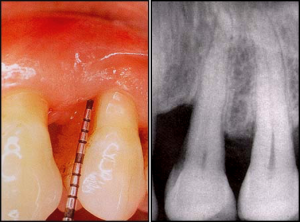

AFTER

Thorough cleaning of root surfaces beneath the gum line to remove plaque and tartar deposits.